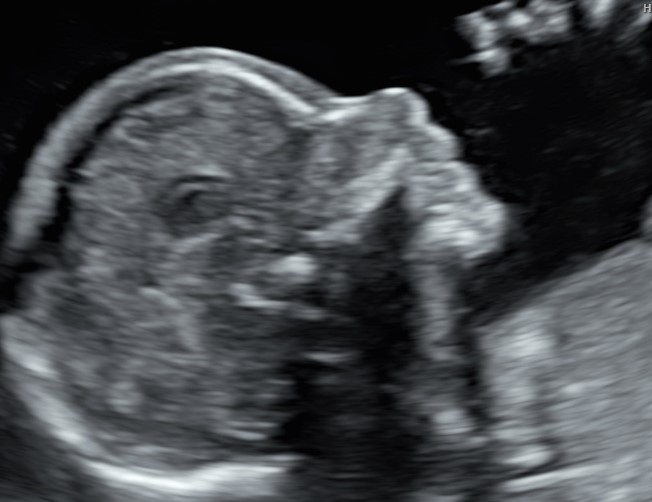

L’ecografia morfologica, come tutte le ecografie ostetriche, deve dare ampio spazio anche ai genitori, alle loro curiosità, al loro bisogno di essere rassicurati, ed è da questa settimana che si possono fare delle bellissime foto in 2D e 3D del volto del piccolo, sia frontalmente che di profilo, innescando invariabili conflitti sulle presunte somiglianze. Se non abbiamo eseguito l’ecografia pre-morfologica, è questo il momento in cui finalmente abbiamo la conferma se il piccolo è une “tesorino” (sinistra) oppure una “tesorina” (destra).